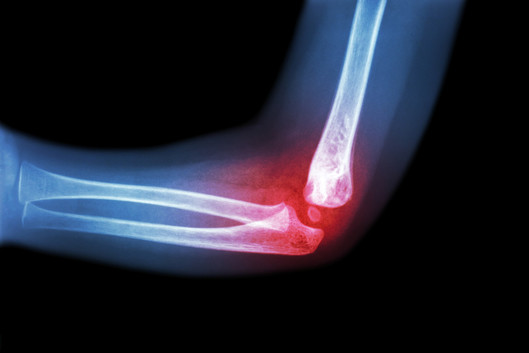

Der Schwerpunkt operativer Eingriffe liegt in der Kinder- und Jugendtraumatologie auf minimalinvasiven, „patientenschonenden“ Verfahren, die mehr und mehr Einzug in die moderne Unfallchirurgie, auch bei Erwachsenen, finden.